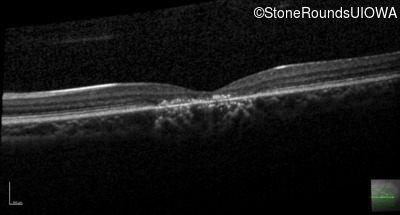

Optical Coherence Tomography - Left - 20/32 +1

Exemplar / OCT Stack

OCT Stack